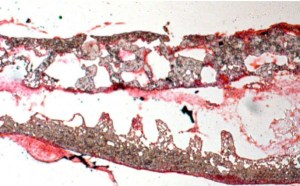

T-VEC recruits immune cells (orange) to attack cancer cells (pink). Photo credit Dr. Andrejs Liepins/SPL.